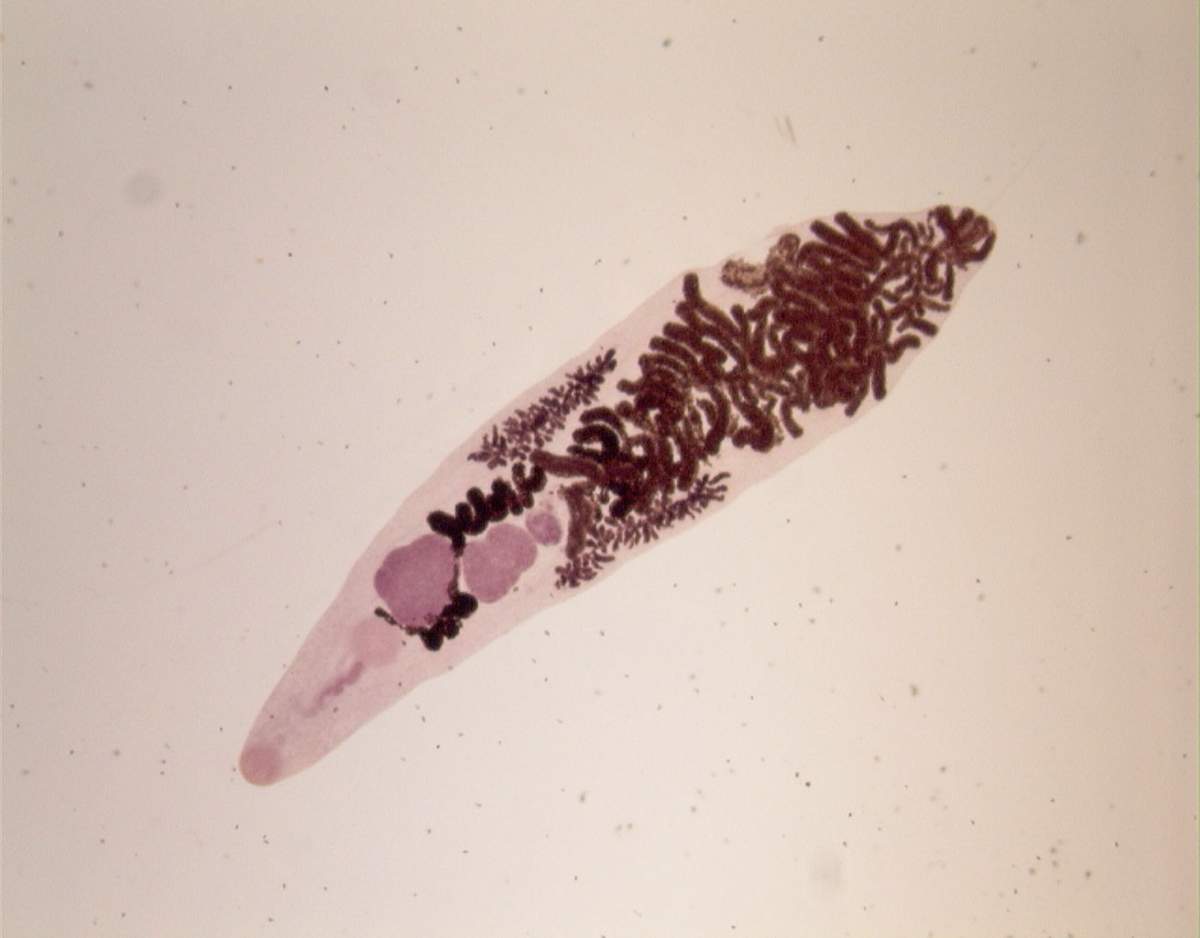

Черви в печени человека: какие паразиты живут в печени и в желчных протоках? В печени человека могут поселиться такие черви – кошачья (сибирская) двуустка, аскариды, лямблии, эхинококки и альвеококки, печеночный сосальщик

двуустка